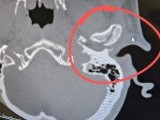

The construction worker was taken to Dell Seton Medical Center where CT scans revealed he sustained a broken jaw and a concussion. Medical examiners found a shard of his jawbone in his ear canal, which was full of blood.